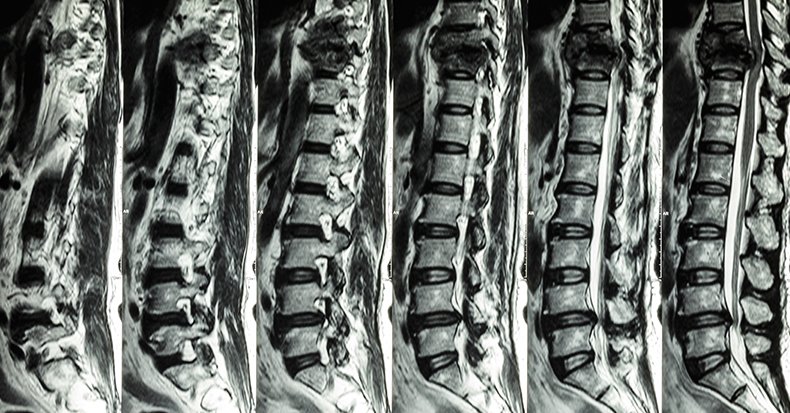

• Improved spinal alignment